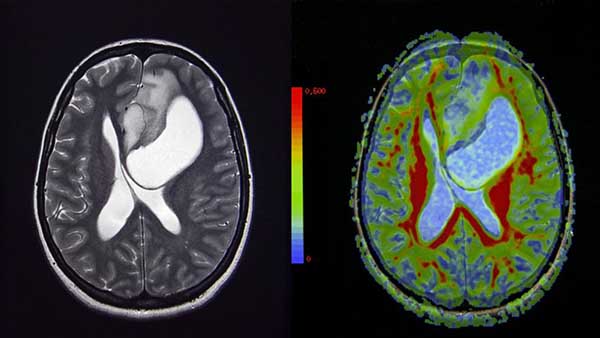

Imagen de un tumor cerebral (semnic / Getty)

Barcelona, 20/12/2018(El Pueblo en Línea) - Una investigación financiada por la Unión Europea y en la que han participado cuatro hospitales europeos, entre ellos Vall d’Hebron, uno de EE.UU. y otro de Israel, ha podido demostrar que existe una posibilidad nueva de tratamiento para el glioblastoma, uno de los cánceres cerebrales más frecuentes y con una esperanza de vida media de 15 meses, según La Vanguardia.

El ensayo -fase I- demuestra que una vacuna personal, con antígenos especialmente fabricados a partir del propio tumor, genera una respuesta inmunitaria a largo plazo en las personas tratadas. “Los pacientes que participaron en el ensayo doblaron su tiempo de supervivencia, pero no podemos asegurar que funcione, sólo que la reacción inmunitaria persiste en el tiempo y que somos capaces de hacer este tratamiento tan complejo y personalizado que permitirá plantear una inmunoterapia individualizada para estos tumores”, resume el neurocirujano de Vall d’Hebron Fran Martínez Ricarte, uno de los participantes en la investigación.

El estudio se publica en la revista Nature y a juicio de los especialistas es un gran paso para un tipo de tumor especialmente agresivo y de mal pronóstico, que desde hace a?os se trata del mismo modo y con escasa eficacia.

En el ensayo participaron 20 pacientes a los que se les había podido sacar todo el tumor. Se les aplicó el tratamiento estándar, con radioterapia y quimioterapia posterior y además les dieron dos tipos de vacunas. La primera se fabricó a partir de las mutaciones genéticas comunes en los 20 tumores extraídos. Se trataba entonces de una vacuna frente a alteraciones compartidas. En una segunda etapa, se fabricó la vacuna específica para cada tumor y se aplicó a cada paciente la suya, tras los primeros ciclos de quimioterapia. “Es muy laborioso y por eso se realizó el tratamiento en esas dos fases”, explica el neurocirujano.

Así se ha podido comprobar que hay una respuesta inmunitaria lo que la convierte en una posible vía de tratamiento. “Pero hasta que no podamos comparar los resultados con un grupo control no podremos saber si ese aumento de supervivencia es real”.